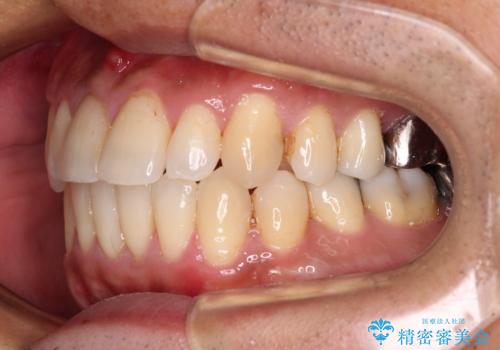

受け口傾向の咬み合わせ 前歯のデコボコをワイヤー矯正で素早く改善

前歯のクロスバイトは、改善の途中で歯髄壊死を起こすリスクが高くなるため、マウスピース矯正よりもワイヤー矯正をお勧めしております。

この患者様もクロスバイトはあっという間に改善され、1年強で速やかに治療を終えることができました。